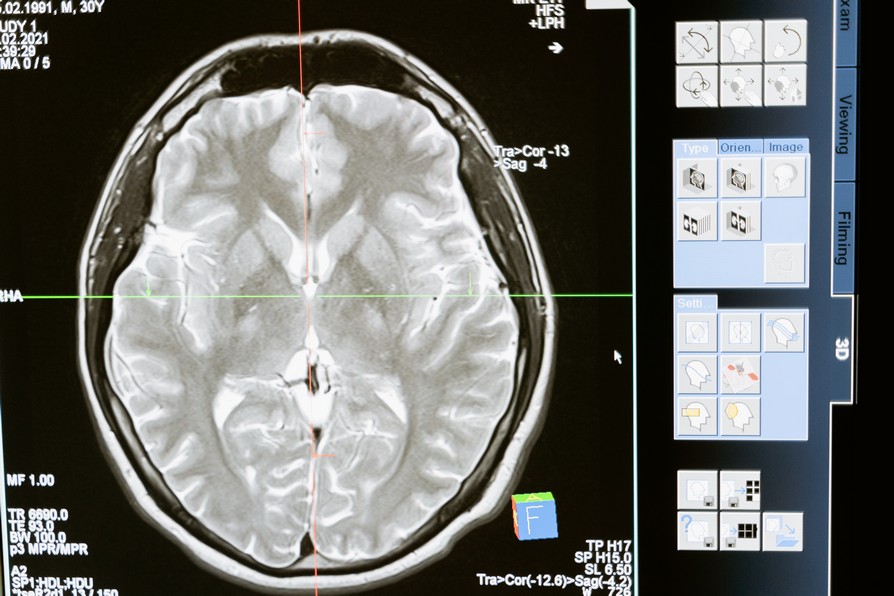

Ct Scan Concussion . If in doubt, sit it out. Brain imaging studies are helping us understand what is going on in the brain. When serious injury is ruled out, you will be sent. a ct scan or other imaging tests may be ordered to determine if there is bleeding in the brain. computed tomography scans, commonly known as ct scans are sometimes ordered to evaluate patients. a computerized tomography (ct) scan of the head is the standard test in adults to assess the brain right after. imaging techniques useful for diagnosing concussion. a concussion will typically be diagnosed using a physical exam, which involves testing vision, hearing, balance, coordination, reflexes,. Determines those that can be discharged promptly, versus those that need a period of observation or.